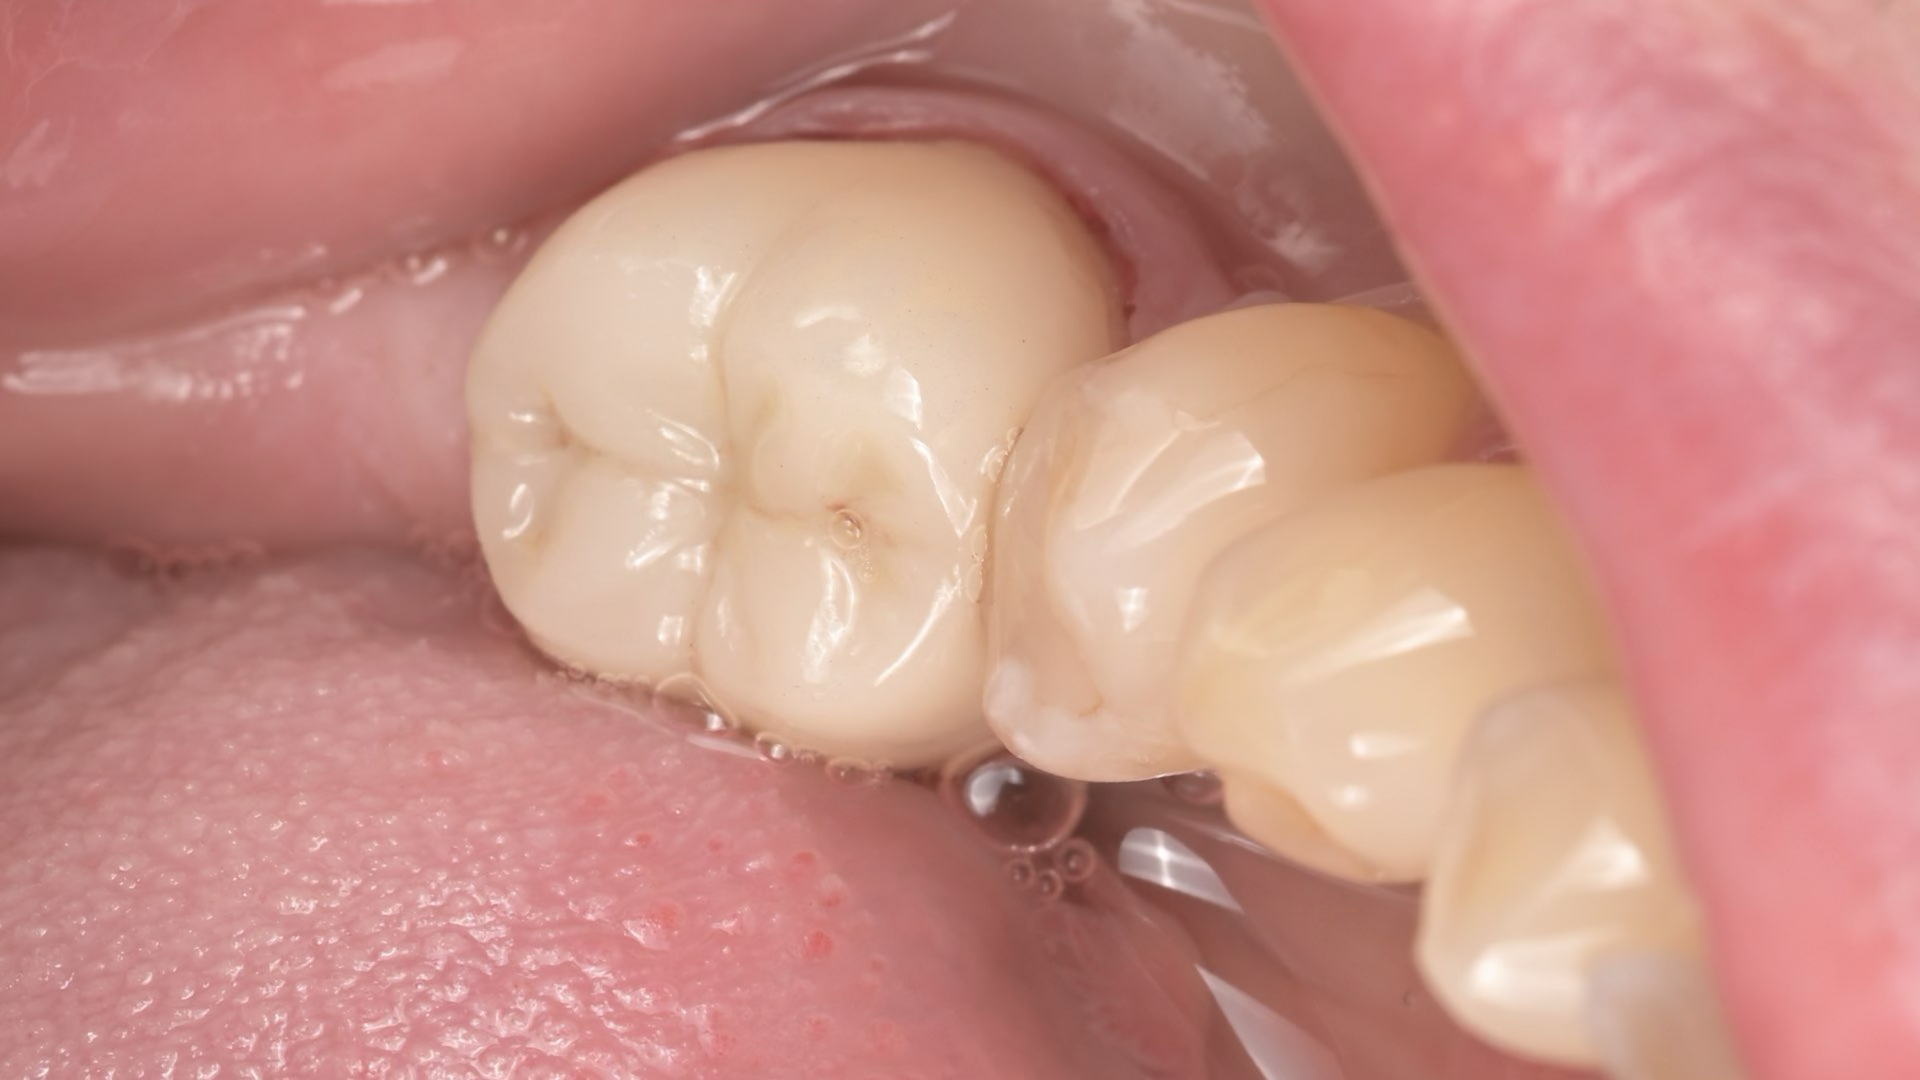

Célja, hogy az elkészült tömések és betétek (inlay, onlay) ugyanolyan erősek és rugalmasak legyenek, mint a természetes fog.

A megmaradó erős fogszövetnek köszönhetően a helyreállított fogak sokkal ellenállóbbak a repedésekkel és töréssel szemben.

A rágóerők egyenletesebben oszlanak el, így a fogat kevesebb stresszhatás éri rágás közben.

Ez a megközelítés hosszú távon stabilabb és tartósabb eredményt biztosít, csökkentve a jövőbeni fogászati beavatkozások szükségességét.

Összefoglalva: Az így elkészült tömések időtállóbbak, pontosabbak és jobban védik a megmaradt foganyagot, mint a hagyományos technikával elkészített tömések, a kutatások alapján, ez a jelenlegi ismereteink szerinti legmodernebb, evidence-based eljárás.